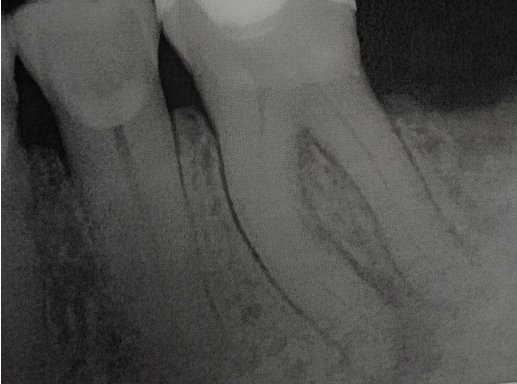

Два года назад опухла десна, зуб начал шататься, врачи сказали, что нужно вырвать зуб, но я не согласился. Потом они сделали надрез и почистили десны от гноя, потом, через несколько месяцев зуб затвердел. Спустя два года начал побаливать по ночам, сегодня сделали рентген, врач говорит нужно вырвать зуб, но мне не хочется.

Возможно в зубе имеется обширный воспалительный процесс, а также воспаление по периодонтальной щели. Данный зуб скорее всего необходимо удалить.